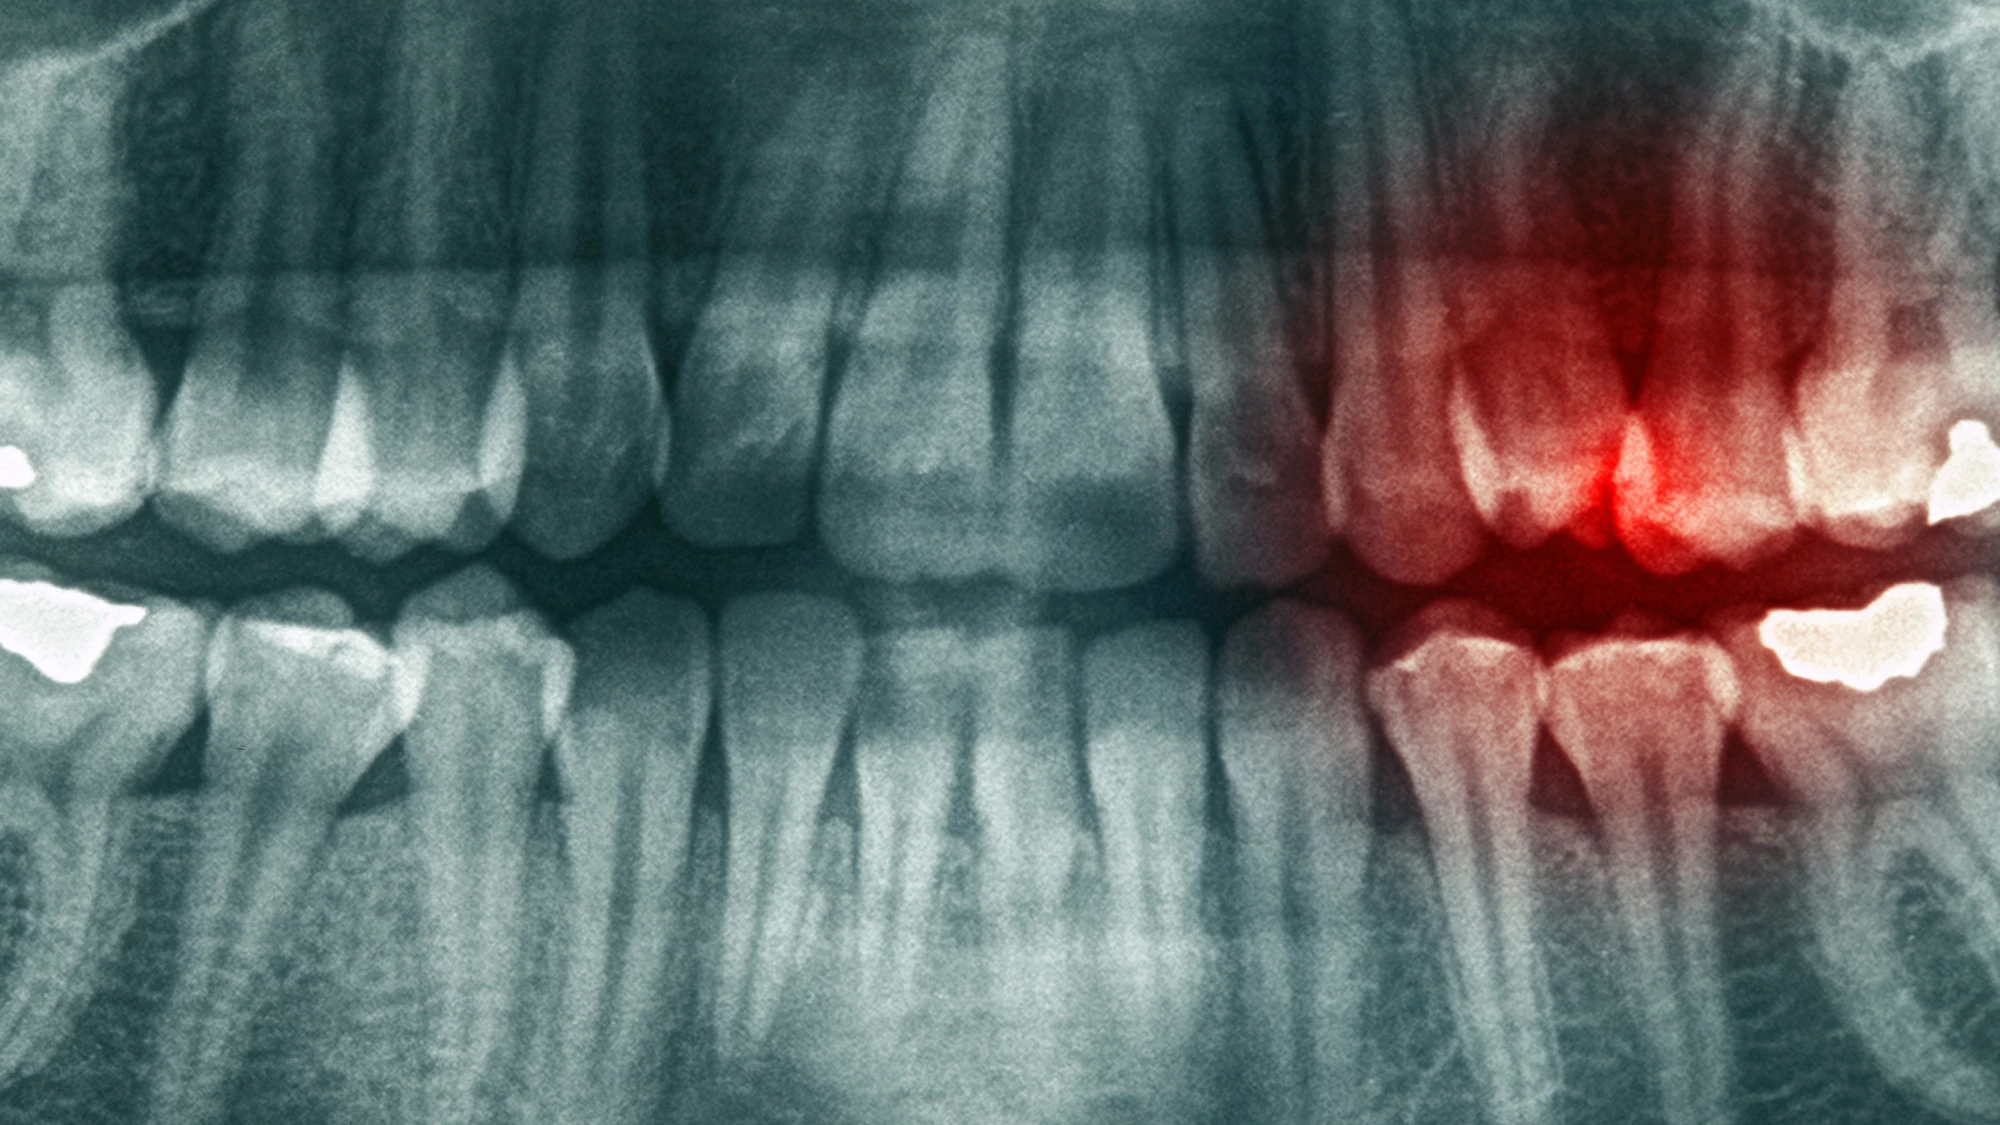

Apical periodontitis (AP) occurs when bacteria reach the tip, or apex, of a tooth root and cause inflammation of the surrounding tissues. It can be caused by tooth decay, trauma, or following dental procedures. If left untreated, it can lead to the destruction and loss of underlying bone and eventual tooth loss.

The rats’ immune responses were analyzed by measuring the inflammatory markers tumor necrosis factor alpha (TNF-⍺) and interleukin-17 (IL-17), both pro-inflammatory cytokines produced by activated immune cells. The researchers observed that the rats with the lowest levels of inflammatory markers were those that swam and received the supplements. Furthermore, that group also had a significantly lower number of osteoclasts, which are the cells responsible for bone loss in pathological conditions like AP. When the researchers took CT scans of the rats’ jaws, they found that the animals who swam and received supplements had the least alveolar bone loss of the three groups. The alveolar bone is the specialized bone in the jaw that surrounds and supports the roots of the teeth.